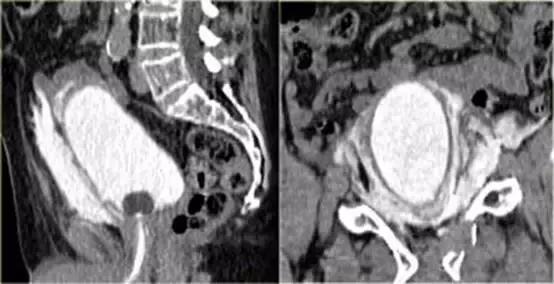

矢状和冠状重建图像

对比剂没有向腹腔内蔓延,膀胱CT 造影敏感性和特异性较高,关键是膀胱充盈要好